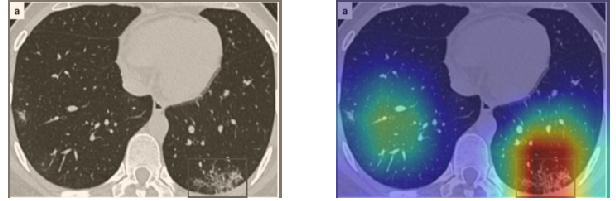

A wide variety of typical and atypical CT abnormalities have been reported for COVID-19 patients in various studies [58, 59]. So, we tested our models on external CT images extracted from these two publications as they feature typical findings of COVID-19 pneumonia marked by specialists. In order to make sure that not any of the extracted images are unintentionally included in our datasets, specifically the COVID19-CT dataset, we use the model trained on the SARS-CoV-2 dataset. First, the InceptionV3 model is employed to classify the extracted CT images. The model is able to correctly classify the given CT images as COVID-19. Second, in order to interpret the model’s generalization capabilities, we apply the Grad-CAM technique to visualize the regions of abnormalities that are considered. By assessing the different CT images in Figure 15, we can see that the model accurately localizes the disease-related regions. Even more interesting is the fact that the model ignores any specific marks in the images like letters and only localizes the COVID-19 related regions. These visual explanations show the success of our models to learn relevant, generic visual features related to COVID-19 and are capable to correctly classify CT images outside the datasets on which they are trained.

Figure 16 shows various CT scans where only one lung is visible. The CT scans are also extracted from the paper [58] and show different CT manifestations of COVID-19 pneumonia marked by red squares. The InceptionV3 model is capable to classify them correctly as COVID-19, although it is trained on CT scans where the entire lung is visible. Intriguingly, when applying Grad-CAM we can see that all regions of abnormalities are accurately localized. This also proves the potential of our model to detect COVID-19 abnormalities in CT images outside the dataset used for training.